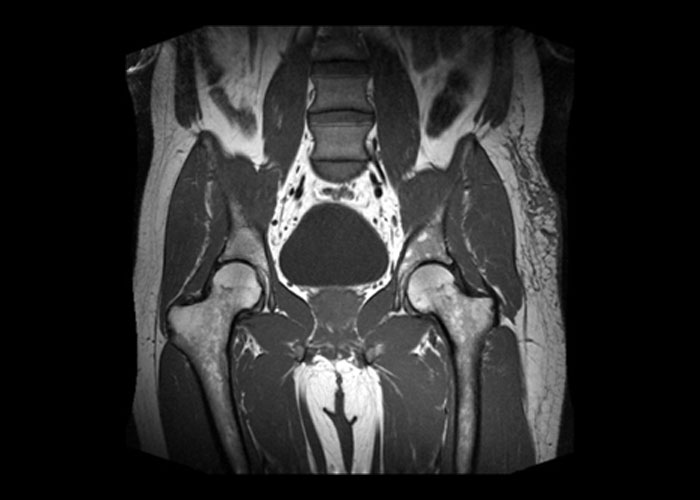

Pelvik MR, güçlü manyetik alanlar ve radyo dalgaları kullanarak alt karın bölgesinin detaylı kesitlerini oluşturan, radyasyon içermeyen bir görüntüleme yöntemidir. Yumuşak dokuları görüntülemedeki başarısı sayesinde, rahim ve yumurtalık yapısını milimetrik hassasiyetle incelememize olanak tanır.

- Miyom ve Polip Takibi: Rahim içerisindeki miyomların yerini, sayısını ve boyutunu netleştirerek cerrahi planlamaya yardımcı olur.

- Çikolata Kistleri (Endometriozis): Endometriozis odaklarının derinliğini ve yayılımını belirlemede en güvenilir yöntemdir.

- Yumurtalık (Over) Kistleri: Kistlerin iyi huylu mu yoksa riskli mi olduğu konusunda detaylı bilgi verir.

- Onkolojik Tarama: Rahim veya rahim ağzı kanseri şüphesi durumunda tümörün evrelenmesinde kullanılır.